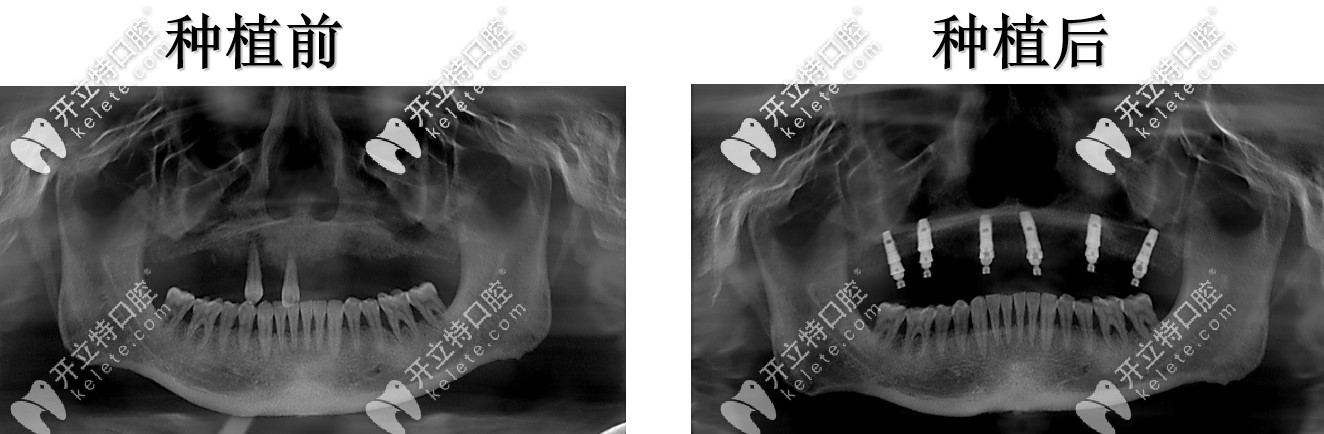

半口種植術(shù)前術(shù)后對(duì)比

這次種牙沒有受太大的罪,有點(diǎn)幸運(yùn),也幸虧了女兒天天在我跟前念叨讓我去整牙看看,有一個(gè)術(shù)前術(shù)后的照片對(duì)比,我覺得沒啥變化,但是裝上牙確實(shí)是感覺挺好,吃東西的感覺又回到了滿口真牙的時(shí)候。

種植牙前后對(duì)比